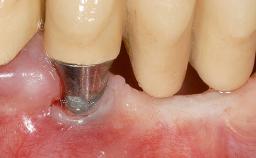

A 30-year-old woman was referred by her general dentist for evaluation of an esthetic complication related to previous implant treatment for congenitally missing maxillary lateral incisors. The patient’s chief complaint was the inadequate esthetic appearance of her smile. The case demonstrates the use of a combined approach to achieve optimal results. Two different flap designs - a tunnel technique and a coronally advanced flap - are employed based on the surgical objectives for the affected site.

Soft Tissue Grafting Yes

Soft Tissue Anatomy Intact Defective

Soft Tissue Contour and Volume Slightly compromised